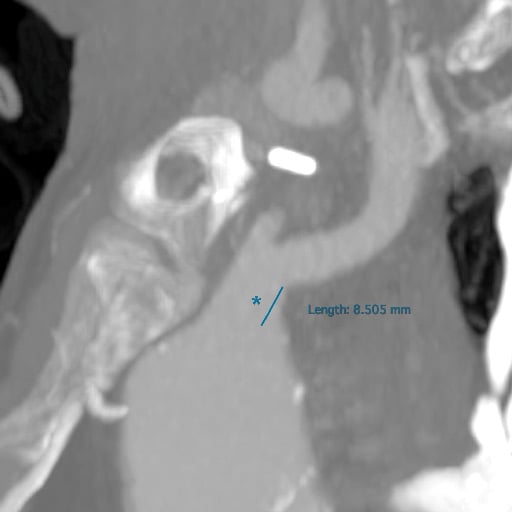

- Short brachiocephalic trunk (< 1 cm)*